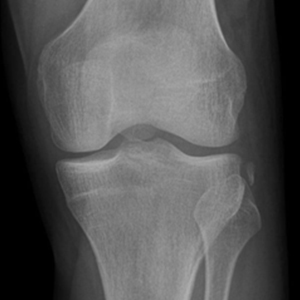

Figure 1

- X-rays: Radiographs can be very important for diagnosing ACL tears. First, they allow the physician to rule out fractures that may be leading to the patient’s symptoms. There are also signs on x-ray, including a “segond” fracture, which is a small avulsion of the capsule that is almost always associated with an ACL tear (see figure 1). One can also perform stress xrays in the setting of a multi-ligament knee injury.